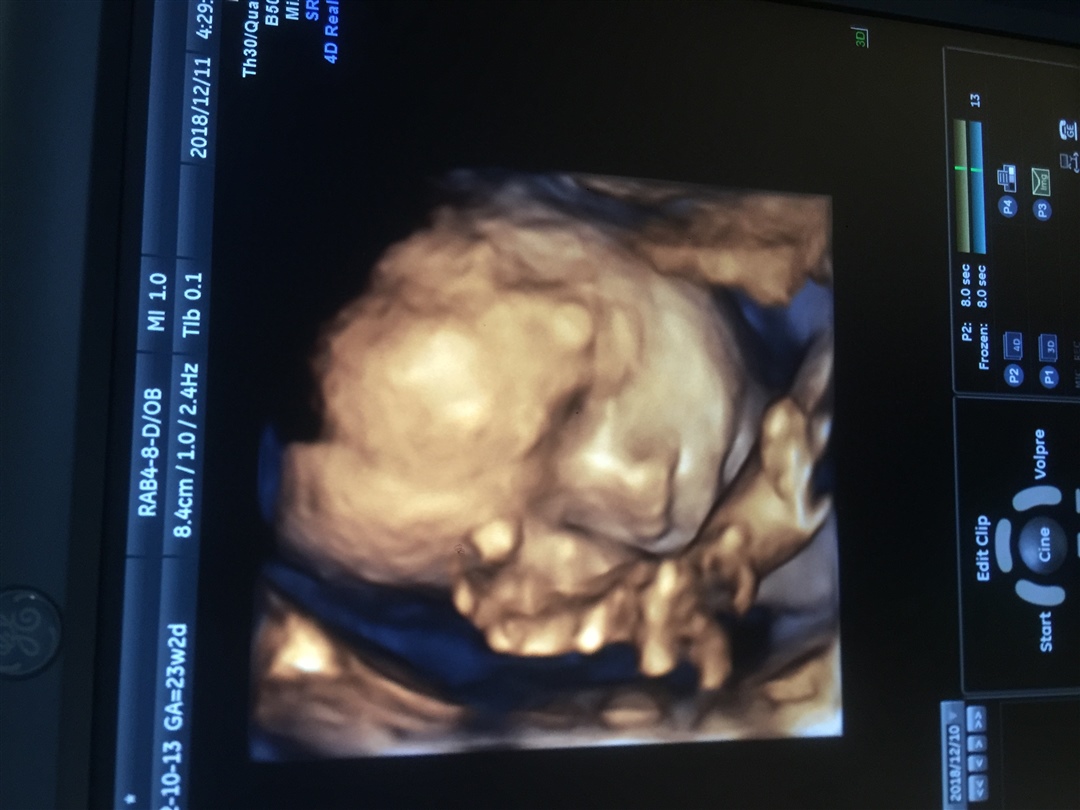

孕30周+1天

孕24周+1天